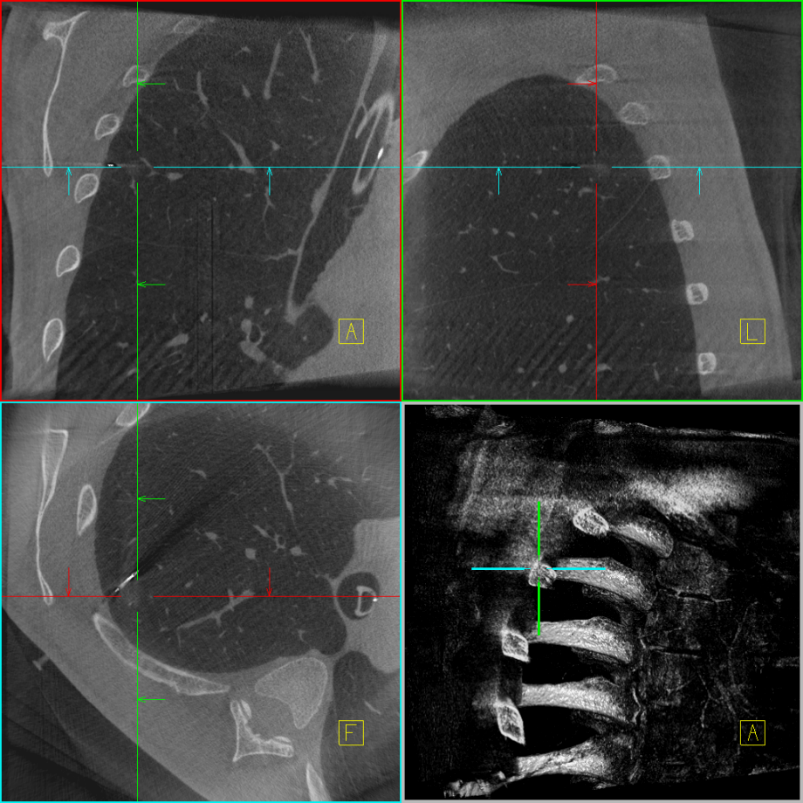

再次扫描,评估定位情况;摆放体位,消毒,开始手术;右上肺后段切除后,切开病灶,可见病灶与定位点毗邻,术中快速病理示右上肺结节为微浸润腺癌,手术顺利,患者安然返回病房。

定位后扫描三维

定位针与病灶位置